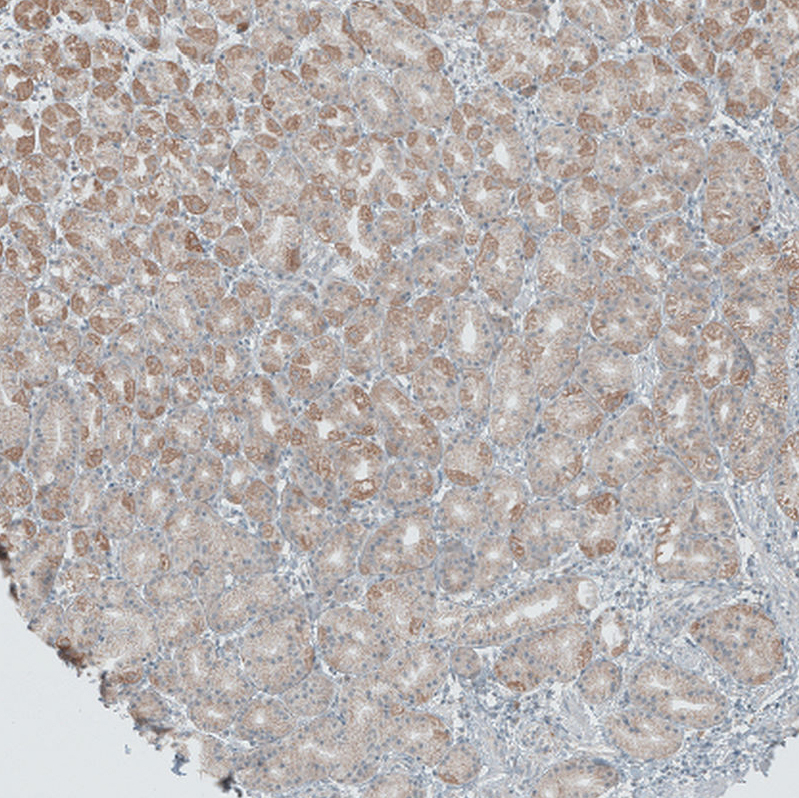

Immunohistochemical staining of human prostate shows moderate to strong cytoplasmic positivity in glandular cells.